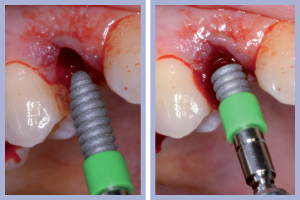

- Figg. 11a, b – Inserimento dell’impianto di destra. Max Stability da 3,75 x 12 mm

- Figg. 12a, b – Impianto di destra inserito

- Figg. 13a, b – Inserimento dell’impianto di sinistra. Max Stability da 3,75 x 12 mm

- Figg. 14a, b – Impianto di sinistra inserito

– Inserimento implantare (Figg. 11-14);

Il posizionamento di due impianti Max Stability da 3,75 mm di diametro e 12 mm di lunghezza ha consentito l’ottenimento di una elevata stabilità primaria, essenziale per portare a termine il carico immediato programmato. Nel caso dell’impianto Max Stability, la forma tronco-conica è associata alla presenza di spire molto prominenti che garantiscono un’elevata stabilizzazione anche in osso di qualità scadente.